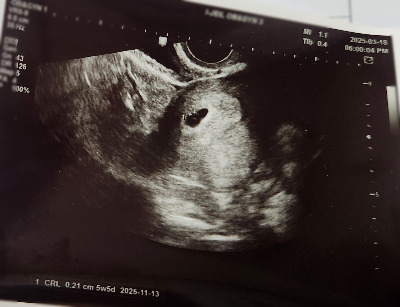

난황이 선명해져서 좋다고 생각했는데 아니었다.

마지막 초음파로부터 3일이나 지났는데 아기는 고작 1mm 남짓 자랐다고 했다. 정상 아기라면 하루에 1mm씩은 자라야 한다고 했다. 아기가 너무 안 크고 있었다. 3일 전 진료에 5주 4일이었는데 아직도 5주 6일이었다. 아기는 0.09mm밖에 자라지 않았다. 아직 심장소리도 잡히지 않았다. 선생님 표정이 어두워졌다. 걱정스러운 목소리로 말씀하셨다.

"나흘 뒤 다시 와서 초음파를 다시 보셔야 할 것 같아요. 그때도 만약 심장소리가 없거나, 아기가 너무 작으면 유산으로 보셔야 할 것 같습니다."